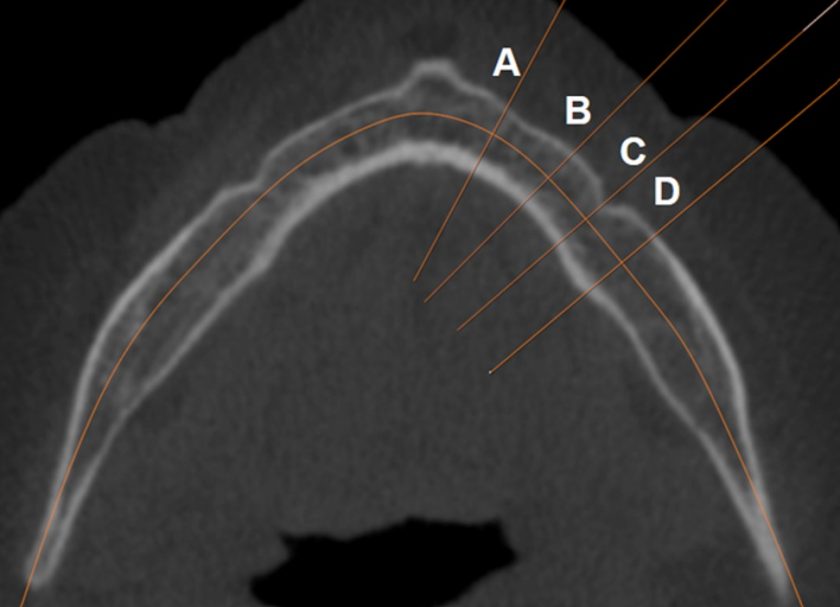

Ir apmācīts un validēts modulārs dziļais neirona tīkls, pamatā izmantota ResNet-101 arhitektūra. Tīkls sastāv no trim secīgiem dziļās apmācības modeļiem klasifikācijas un diviem regresijas uzdevumu risināšanai. Pirmais spēj atlasīt nepieciešamo apakšžokļa kaula griezumu KSDT attēlos aksiālā griezumā, kur vislabāk redzama foremen mentale. Tīkla apmācības precizitāte 98.85% (39 epohas), validācijas precizitāte 93.99% (35 epohas). Otrs veic apakšžokļa kaula griezumus pēc iepriekš definētiem attālumiem, iegūstot apakšžokļa šķērsgriezuma laukuma attēlus. Trešais veic apakšžokļa kortikālā kaula biezumu mērījumus.